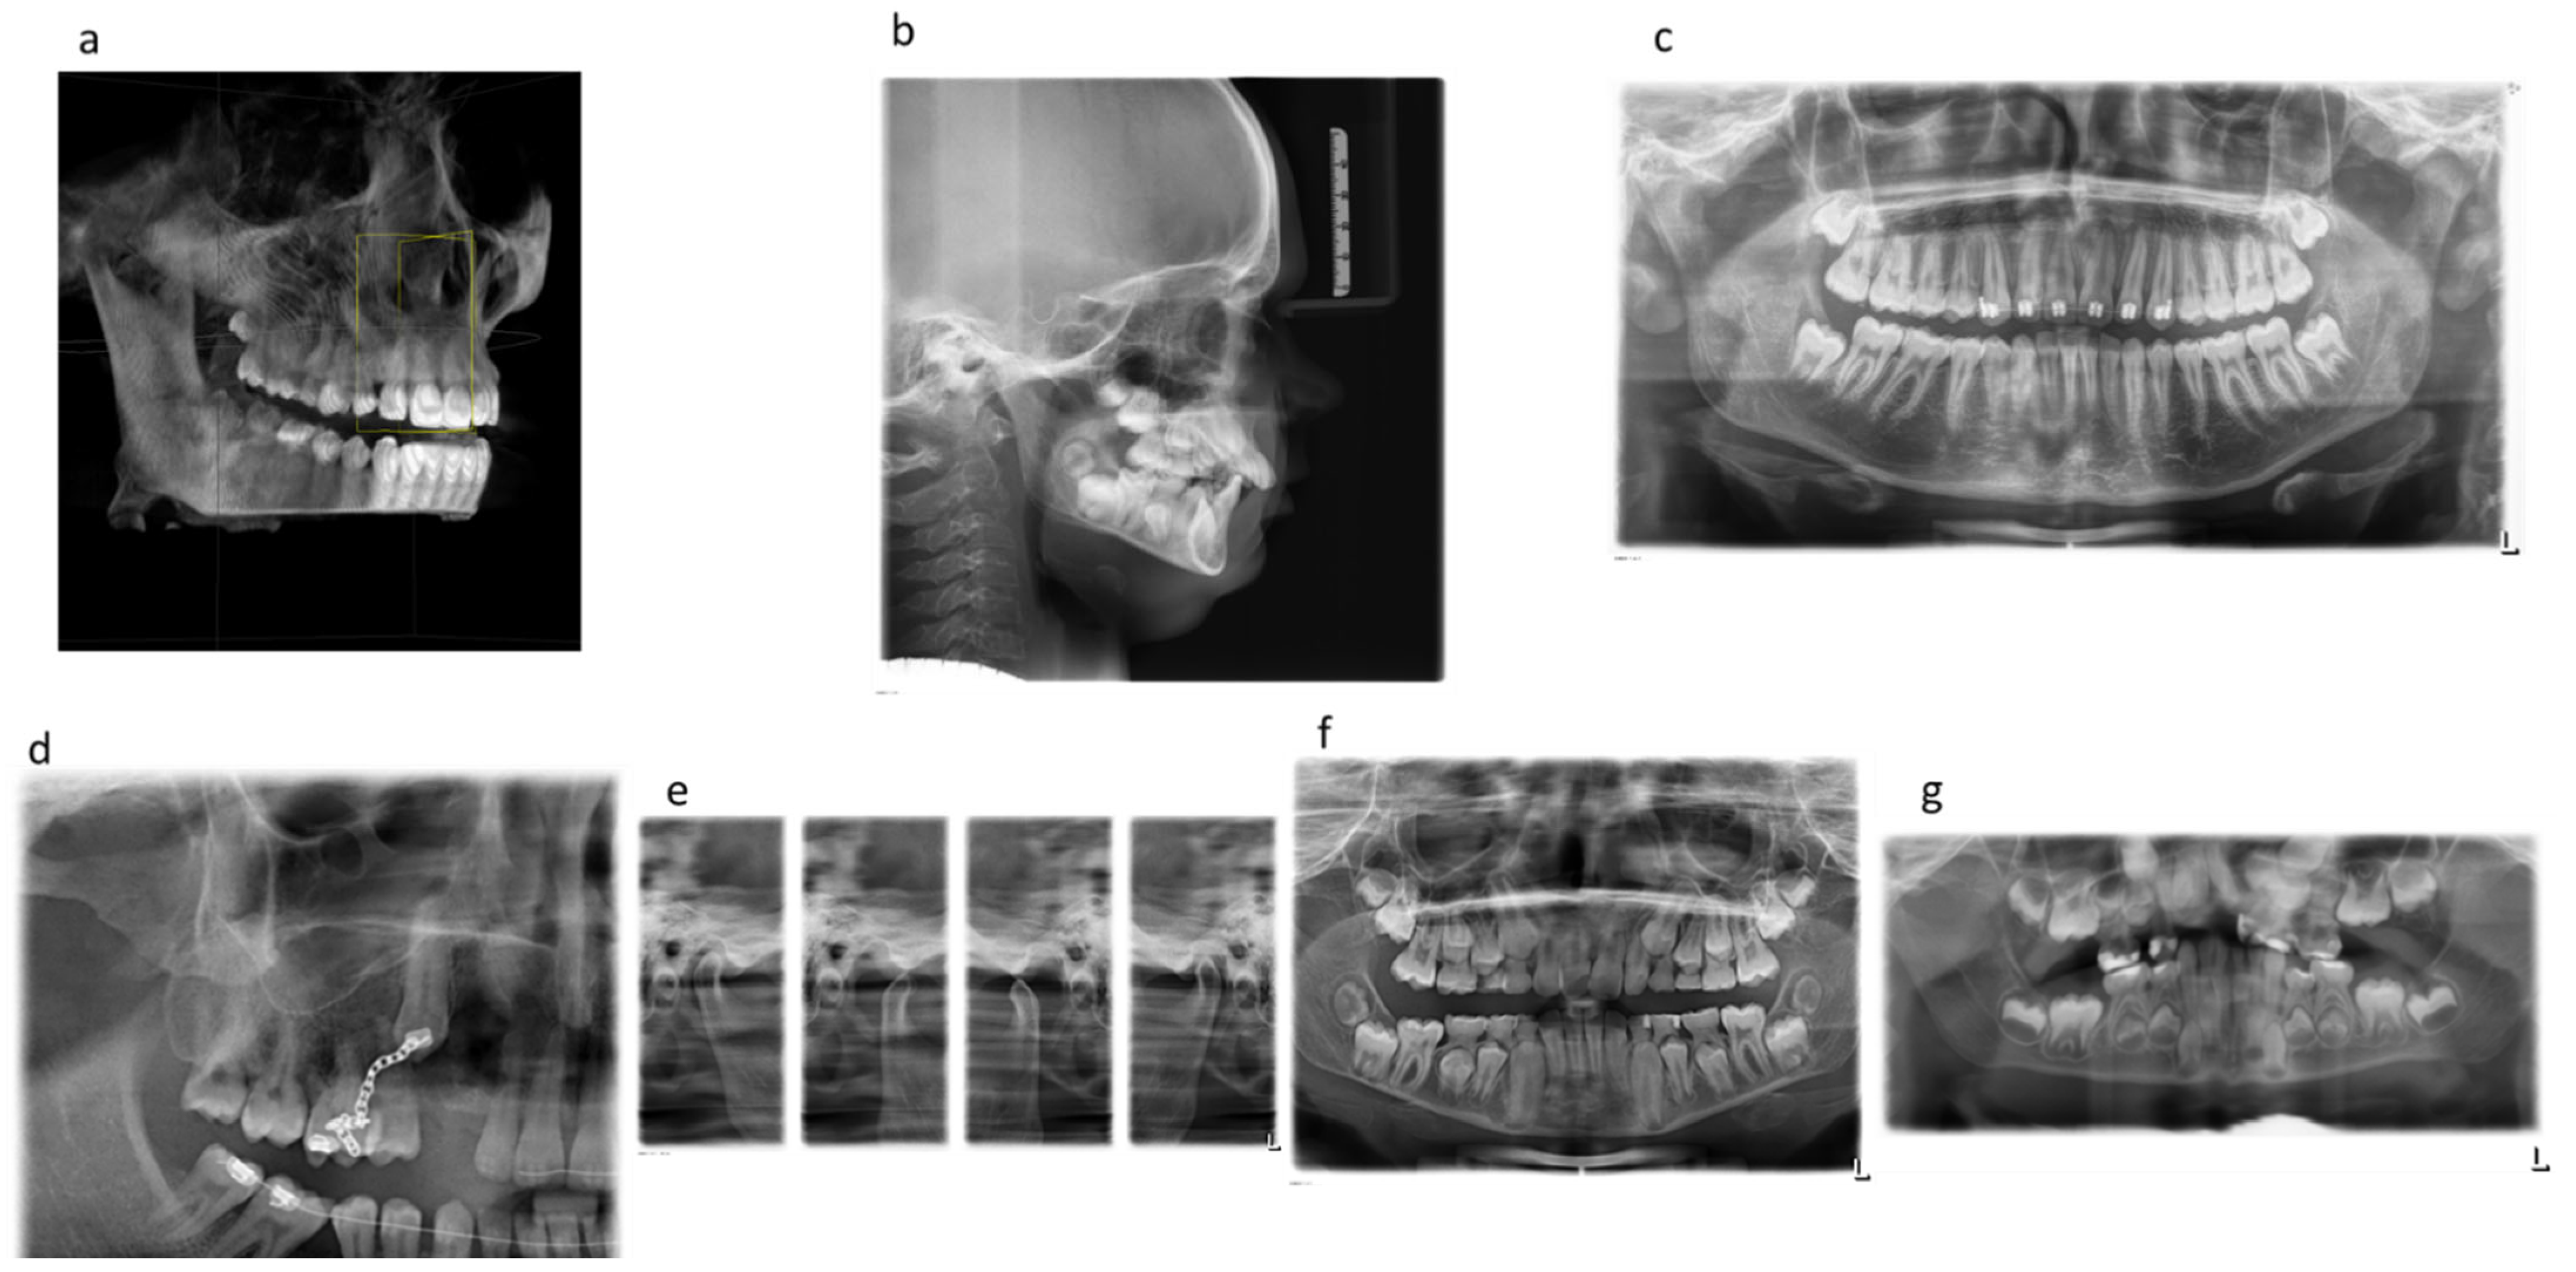

Figure 1 shows examples of the extraoral dental X-ray images analyzed (Figure 1).

Figure 1. Shows examples of the extraoral dental X-ray images analyzed (Figure 1). Examples of the extraoral X-ray images analyzed: (a) CBCT, (b) lateral cephalogram, (c) OPG standard, (d) OPG without TMJ left and half OPG image, (e) OPG TMJ program, (f) OPG without TMJ right and left, (g) OPG child.